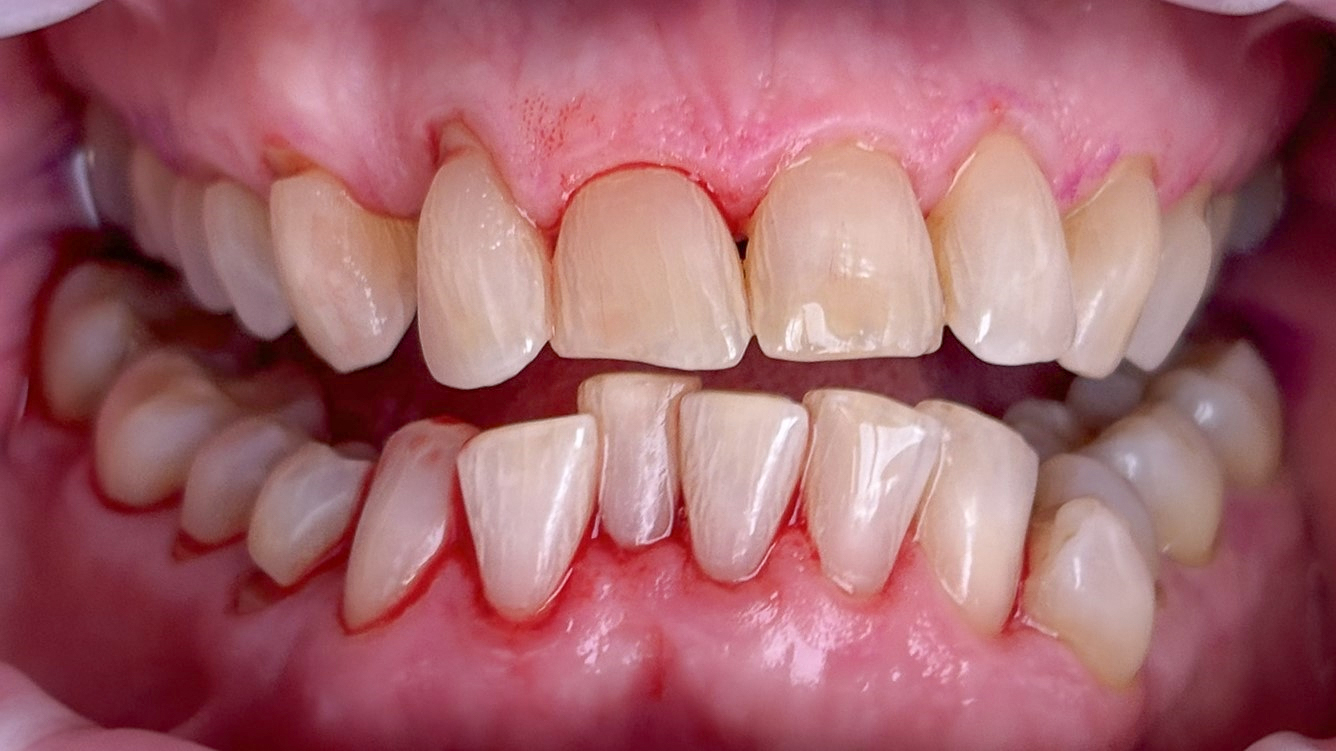

Die Behandlung von Parodontitis basiert primär auf der effektiven Entfernung weicher (Biofilm) und harter Beläge (Zahnstein) von oralen Oberflächen (35). Dabei sollte der Biofilm als ätiologischer Faktor im Vordergrund stehen (1, 36). Die Maßnahmen führen bei den meisten Patienten sowohl in der Initial-, als auch in der nachfolgenden unterstützenden Therapie (UPT) vorübergehend zu mikrobiellen und immunologischen Veränderungen, die mit Gesundheit vereinbar sind (36-39). Auch hier sind exakte Zeiträume variabel und von individuellen Risikofaktoren abhängig (40). Das Biofilm-Management im Rahmen der Parodontitis-Therapie muss wie in der primären Prophylaxe von einem systematischen professionellen Konzept begleitet werden und ist auch bei vorbelasteten Patienten erfolgreich (Abb. 7a+b, 8a+b) (35, 39, 41). Wie in der primären Prophylaxe liegen zu Maßnahmen des Risikofaktoren-Managements in der Parodontitis-Therapie nur begrenzte Daten vor (19).